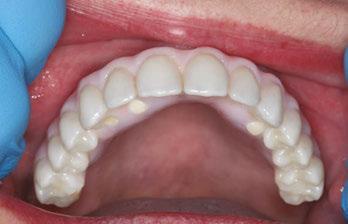

recommended by the manufacturer prior to beginning the definitive prosthetic treatment. Maxillary and man dibular implant-retained overdentures were fabricated using traditional indirect techniques. Both prostheses included metal frameworks for strength and long-term survival, and the LOCATOR housing was picked up chairside at the time of delivery.

We discussed the possibility of changing the type of prosthesis on the maxilla from removable to fixed. We explained to the patient the availability of a novel attachment system utilizing his existing LOCATOR abut ments, and he expressed excitement about the possibil ity. A new maxillary complete denture was fabricated around the LOCATOR abutment utilizing the indirect technique and conventional procedures. This time the denture did not have a metal-reinforcing framework since it will be converted into a fixed prosthesis.

Figures 3A and 3B: 3A. The prosthesis was trimmed and adjusted to eliminate the palate and flanges to convert into a fixed prosthesis. 3B. Processing inserts were replaced with LOCATOR FIXED (Zest Dental Solutions) inserts

Figures 4A and 4B: 4A. Before extractions and implants. 4B. After surgical procedures and prosthetic conversion into a fixed full-arch prosthesis